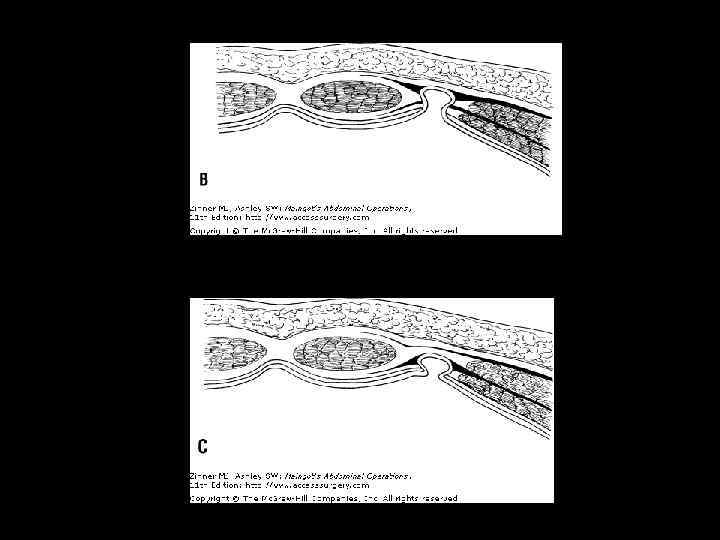

ВАРИАНТЫ ФИКСАЦИИ ТРАНСПЛАНТАТОВ • sublay • inlay • onlay